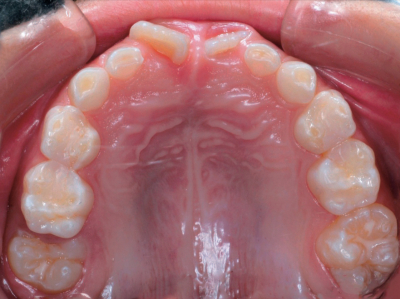

7歳の男児。初診時の口腔内写真とエックス線写真を別に示す。そのままにした場合に予測されるのはどれか。2つ選べ。

a. Dの早期脱落

b. Eの晩期残存

c. 5の萌出余地不足

d. 6の近心転位

e. 7の萌出遅延